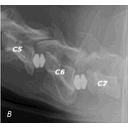

SyndromeWobbler1.jpg

SyndromeWobbler2.jpg